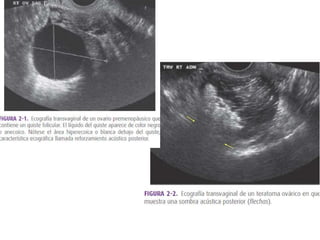

PATOLOGÍA DE OVARIOS ECOESTRUCTURA Normal: borde regular, folículos en distintas etapas de desarrollo, estroma isoecoico. Multifolicular: muchos folículos dispersos en todo el estroma, poco estroma Poliquístico: estroma hiperecoico, folículos en la periferia de 6 – 8 mm en número mayor de 6 y aumento de volumen. Masa ovárica

• 76.

Criterios de evaluaciónde una Masa Ovárica: Biometría ECO estructura: quística, compleja (ecomixta), sólida. Bilateralidad Presencia de tabiques Presencia de papilas Borde externo y grosor Presencia de tejido ovárico indemne Ascitis

Evaluación de masaovárica ECOGRAFIA BENIGNO MALIGNO TAMAÑO < 5 CM > 5 CM CONTORNO BIEN DEFINIDO MAL DEFINIDO PARED FINA CONTENIDO QUISTICO SOLIDO, COMPLEJO SEPTOS FINOS SEPTOS GRUESOS, PAPILAS,NODULOS OTROS ASCITIS